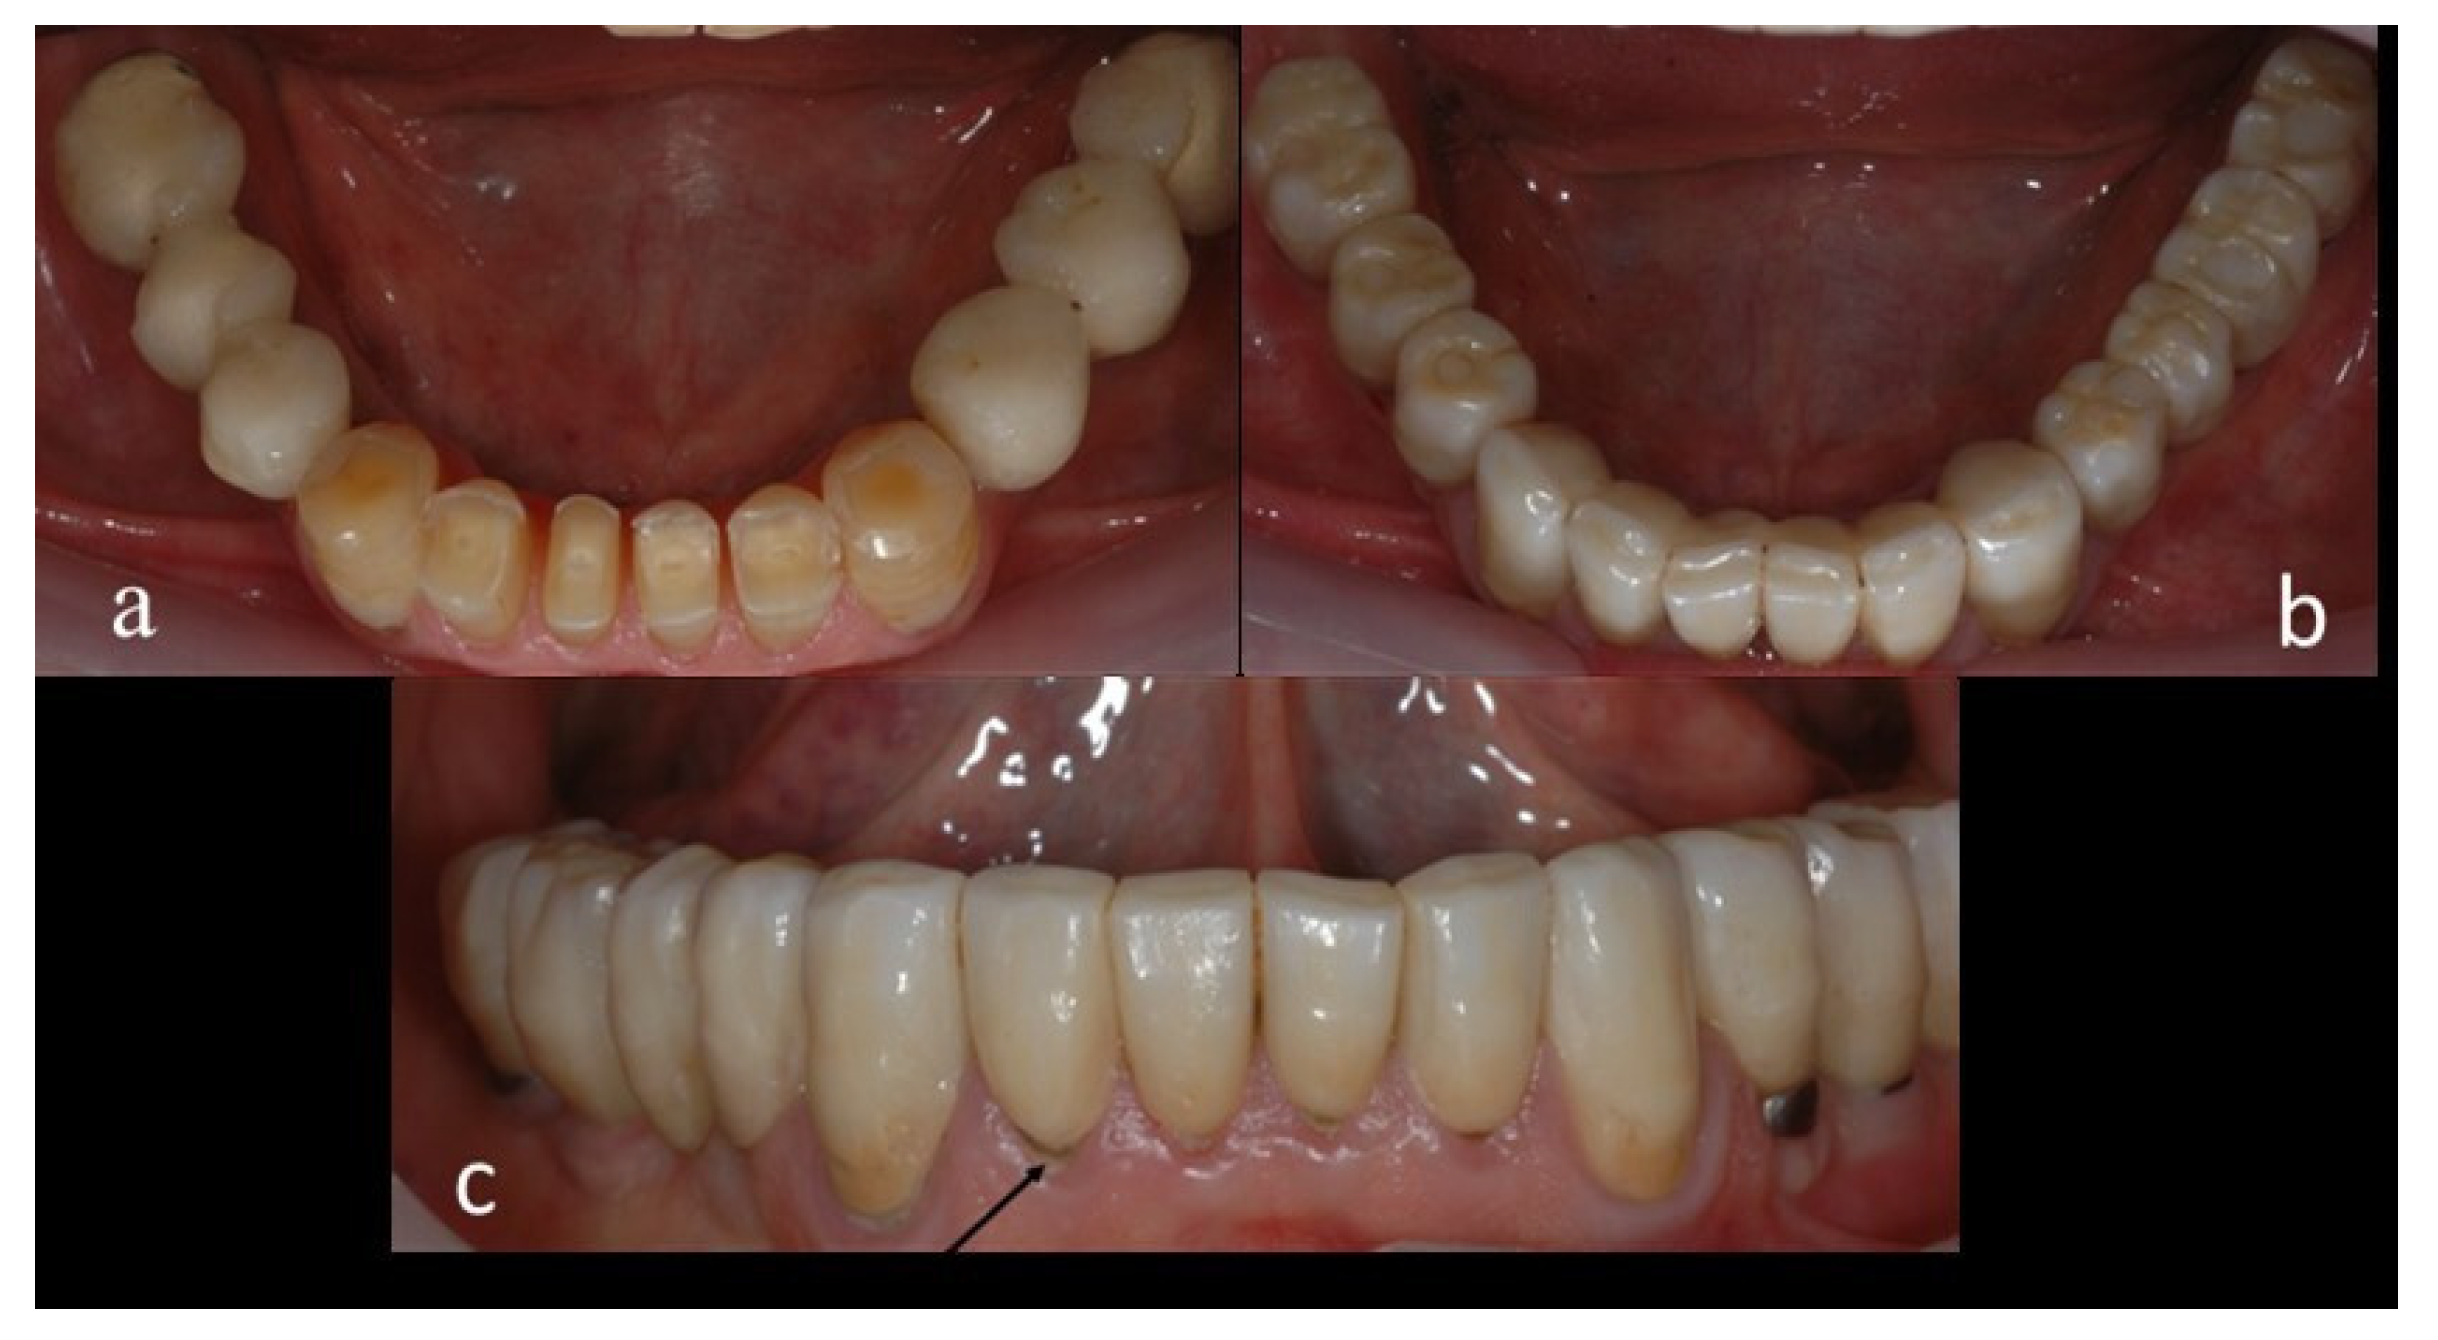

2.4. Methods

2.5. Clinical and Radiographic Assessments and Classification of Observed Events at the Recall Appointment